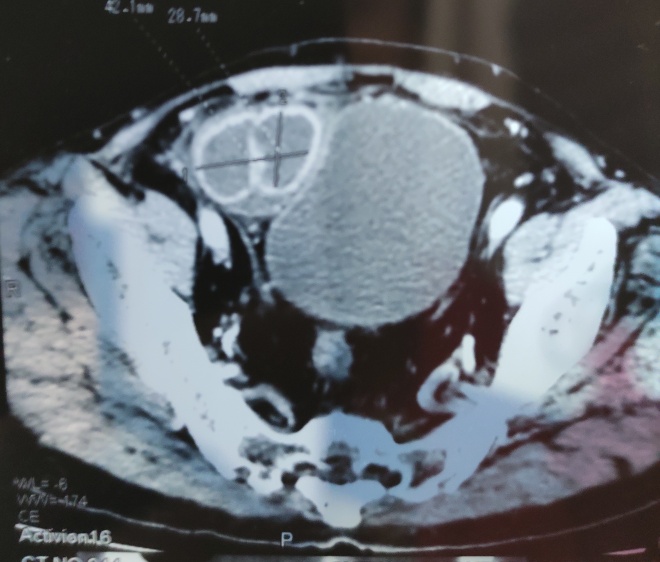

An elderly man presented with a history of colicky abdominal pain and vomiting of 5 days duration. He had a history of exploratory laparotomy for duodenal perforation peritonitis some 20-30 years back. He was having left hemi-paresis due to a stroke 2 years back. He also had history of left uncomplicated inguinal hernia for the last 3 years. On examination, he was dehydrated with a heart rate of 100bpm, blood pressure of 120/86mmHg, and a temperature of 370C. His abdomen was distended, mildly tender and having a previous long midline incision scar. There was also a small, direct, reducible, uncomplicated, left inguinal hernia. Blood tests showed leucocytosis. Plain film radiography showed distended small-bowel loops with air-fluid levels consistent with a small-bowel obstruction. Adhesional small-bowel obstruction was suspected clinically. C.T scan abdomen showed dilated small bowel loops. The coronal C.T image (figure 1) demonstrated a U – shaped bowel loop with a sac – like appearance, on the right side of lower abdomen just over the urinary bladder and pressing it. The axial C.T image (figure 2) showed two transition points of the pseudo-encapsulated small bowel loop above the urinary bladder. The patient underwent exploratory laparotomy and intra-operatively small-bowel obstruction due to right internal Supravesical hernia (Figure 3), was found. The closed loop obstruction had caused strangulation (Figure 4) and hence resection anastomosis of involved ileal loop was done due to doubtful viability. The hernia defect (Figure 5) was closed with interrupted 1/0 Prolene stitches. The patient recovered uneventfully and was discharged on 8th postoperative day.

Figure 2. Axial CT scan showing two transition points of the pseudo-encapsulated small bowel loop.